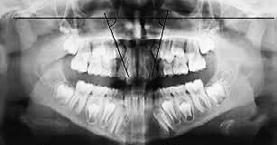

b) Análisis radiográficos, periapicales, ortopantomográficos, oclusales, lateral de cráneo, anteroposterior de cráneo.

c) Estudio y análisis tomográfico en tercera dimensión del cráneo a nivel maxilar y mandibular (Figura 24).